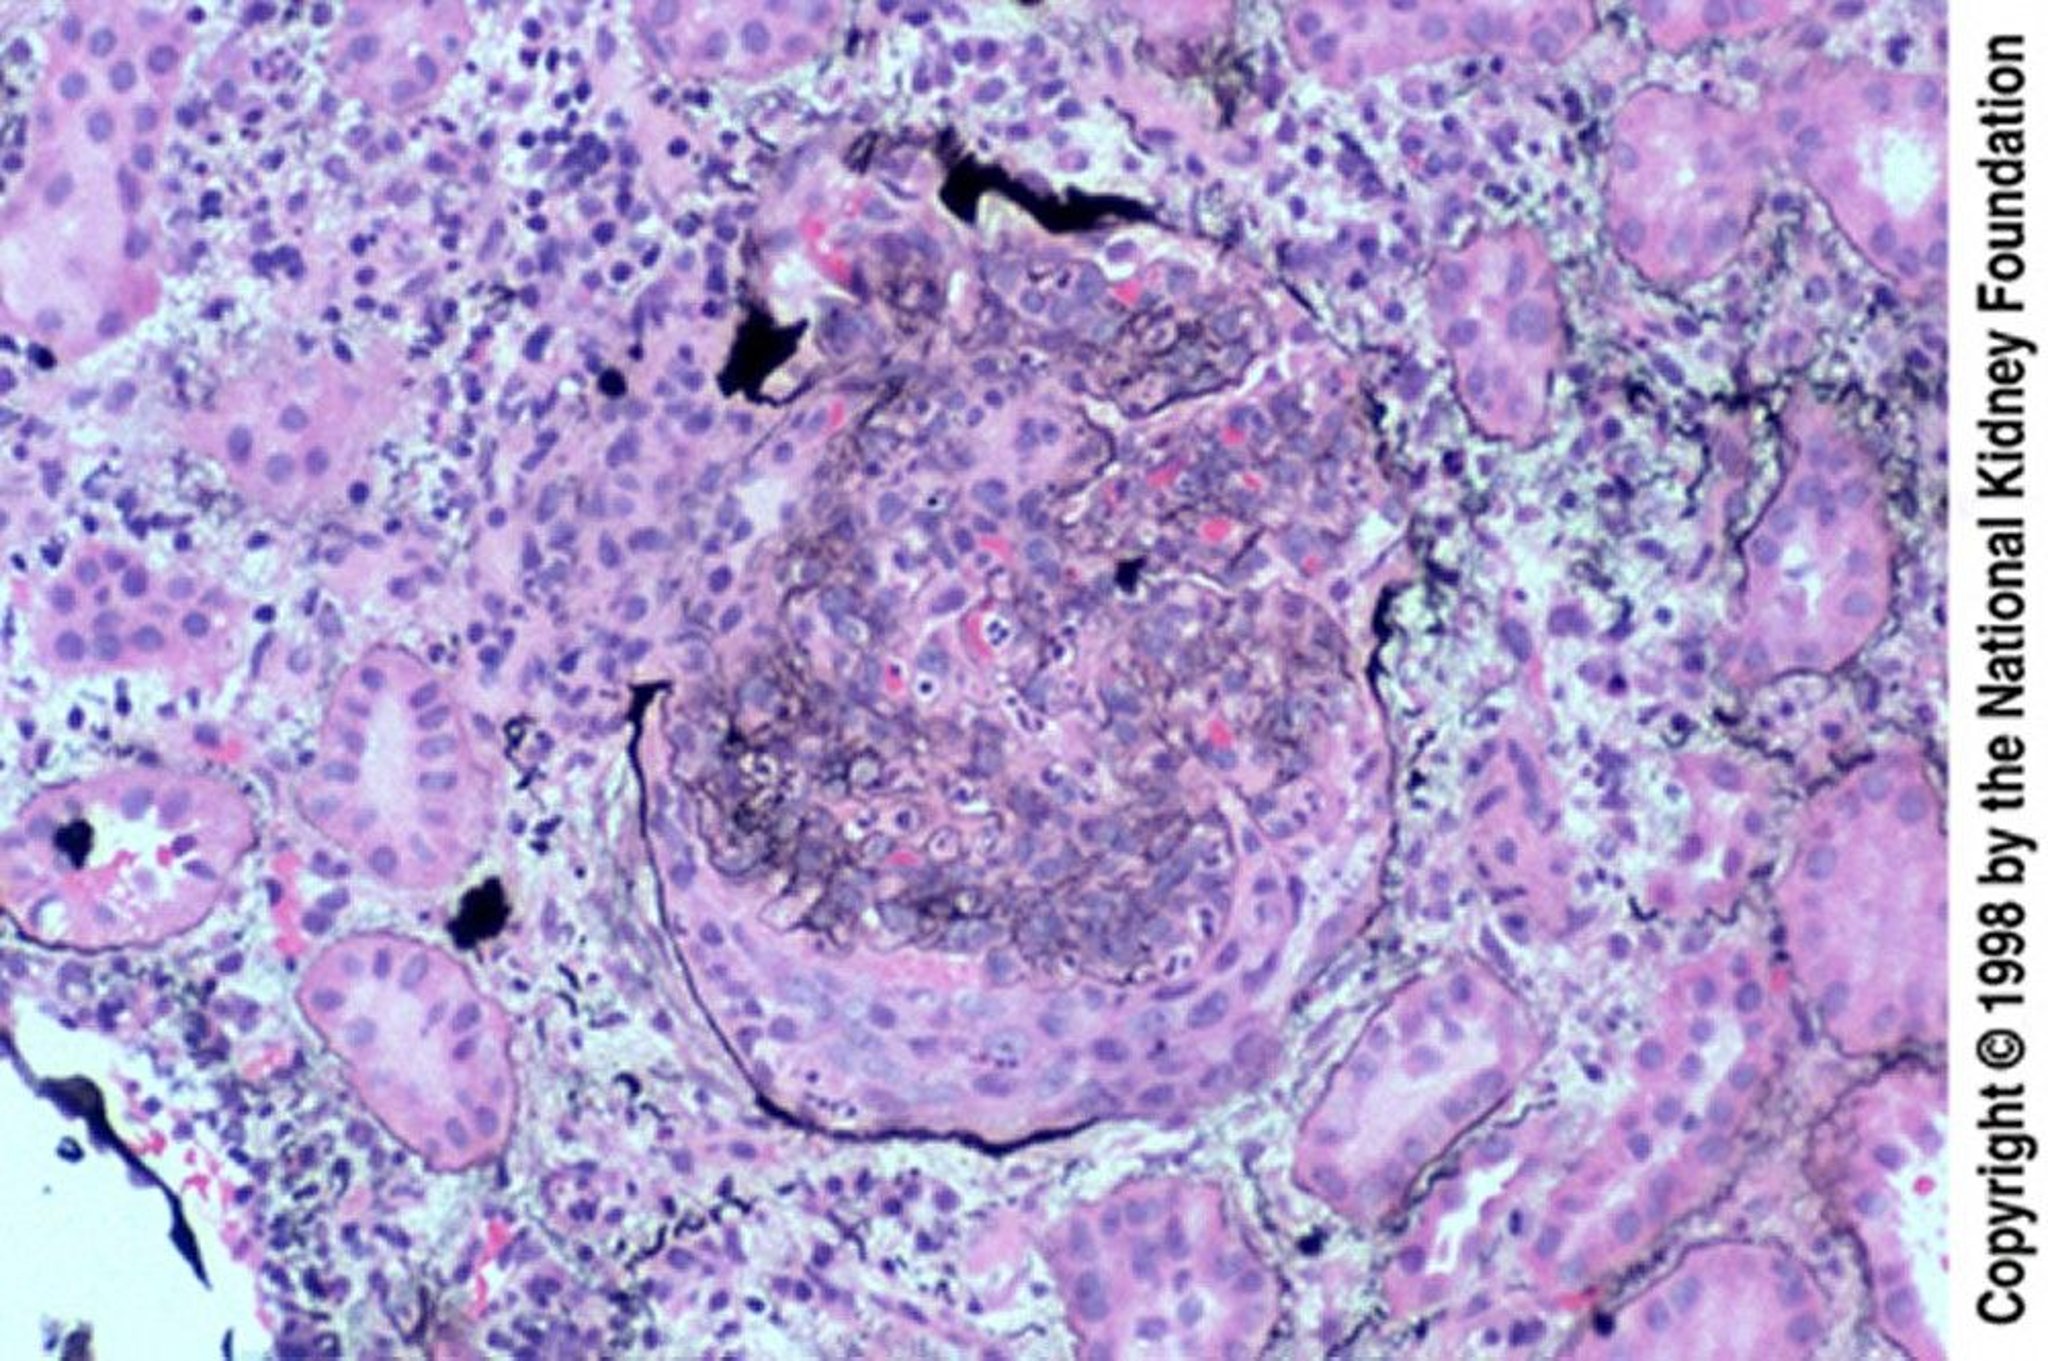

Postinfectious Glomerulonephritis (Epithelial Crescents)

Epithelial crescents are especially common when biopsy occurs late, after a failed response to treatment. The crescent has ruptured Bowman capsule (Jones silver stain, ×200).

Image provided by Agnes Fogo, MD, and the American Journal of Kidney Diseases' Atlas of Renal Pathology (see www.ajkd.org).